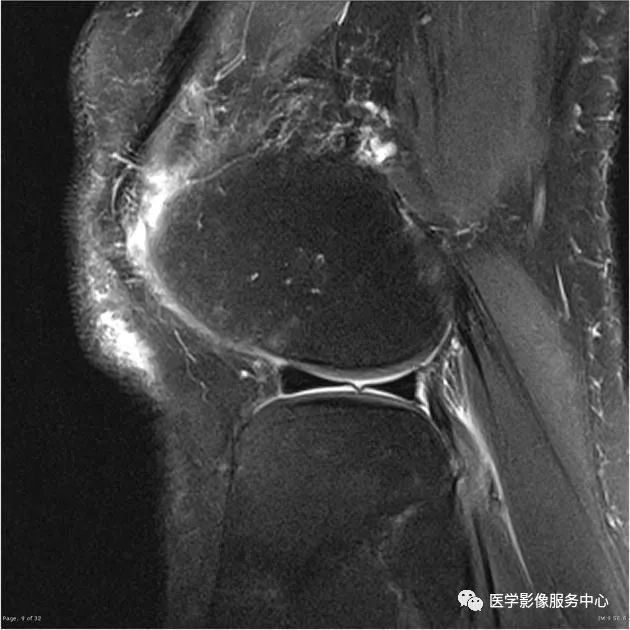

七、腘肌腱

外侧半月板后角处的腘肌腱裂孔可被误认为3度半月板撕裂信号。

A:冠状位MRI显示腘肌腱裂孔(白色宽箭头)与腘肌腱(白色细箭头);

B:冠状位MRI显示腘肌腱(白色箭头)穿过腘肌腱裂孔;

C:矢状位MRI显示腘肌腱(白色箭头),

D:矢状位MRI显示腘肌腱(白色箭头)